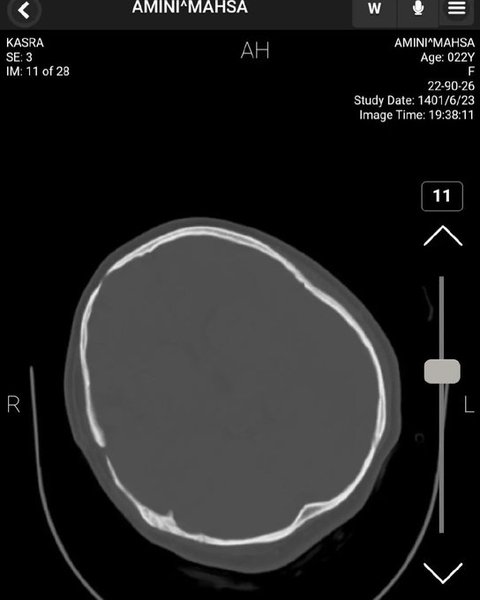

У Twitter якогось Мохаммада, який представився нейрохірургом, опубліковано знімки томографії головного мозку Махси з коментарями.

Згідно з висновком нейрохірурга, на КТ голови Махси не виявлено жодних ознак травми мозку, черепної коробки та кровотечі. На знімках видно сліди зробленої раніше операції.

КТ голови Махси Аміні

Комп'ютерна томографія мозку Аміні

Знімки КТ підтверджують, що черепно-мозкової травми у Махси Аміні не було

"Ознаки хірургічного втручання є, вони свідчать про лобово-скроневу краніотомію з короткочасною атрофією м'язів та зміни м'яких тканин", — коментує хірург.

Так, за даними нейрохірурга, смерть Махси не могла статися від травм головного мозку.